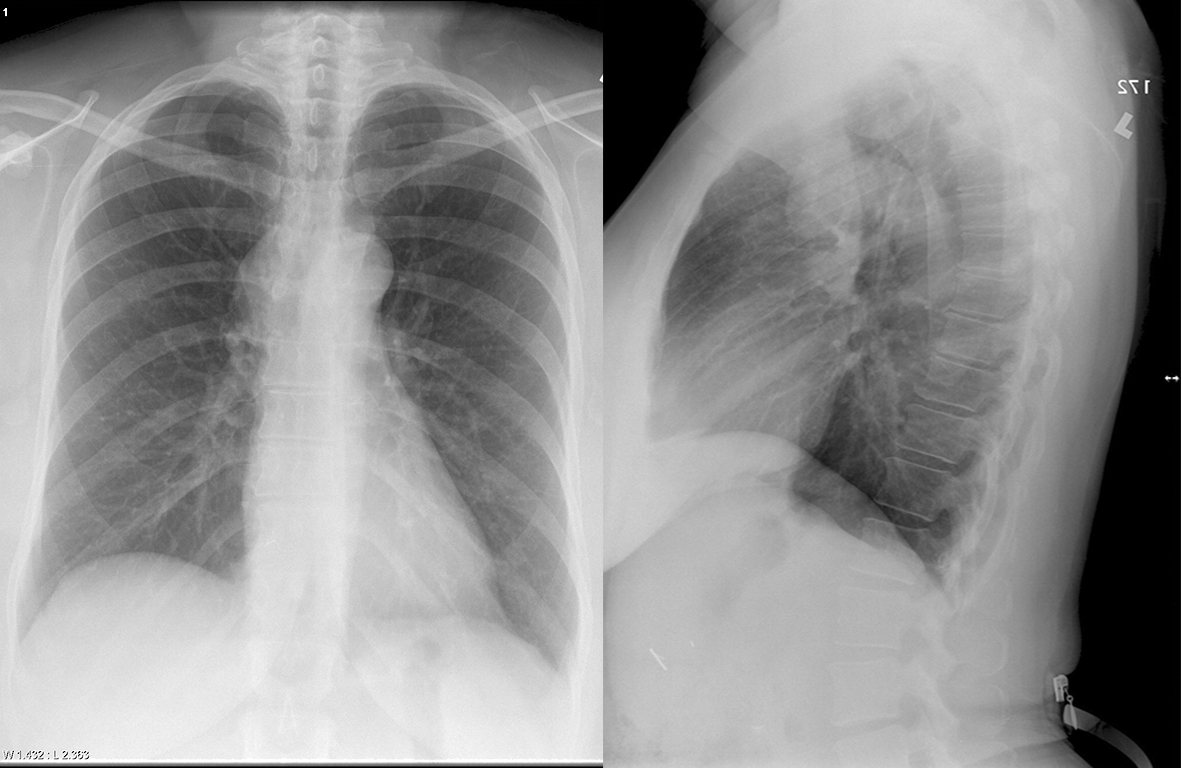

Bronchogenic cyst

Br cyst Pa and Lat